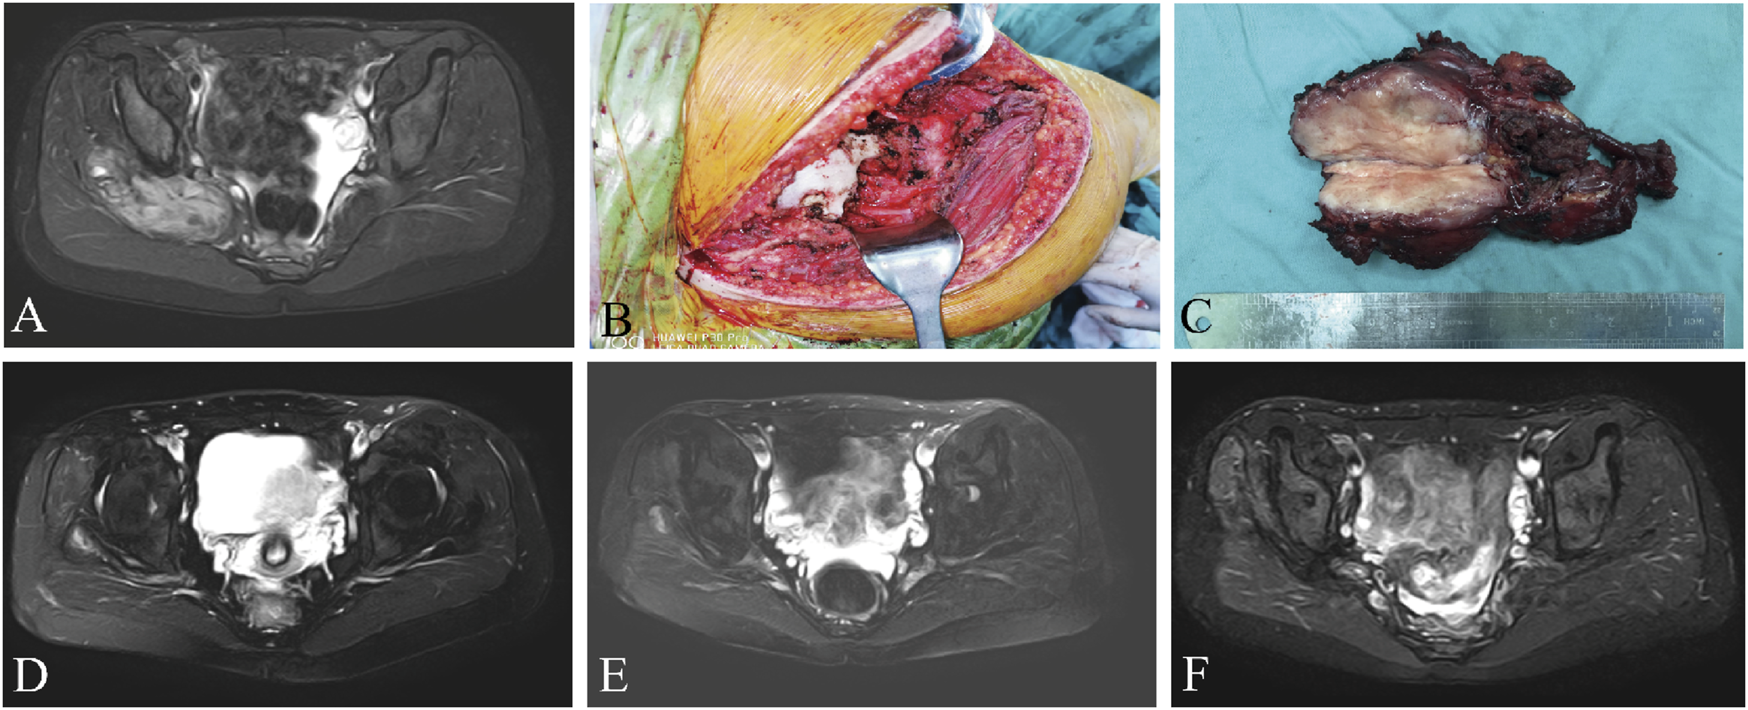

The median RFS was 31 months and the 3-year RFS rate was 37.7% in the surgery alone cohort; the median RFS was 42 months and the 3-year RFS rate was 72.6% in the surgery plus anlotinib cohort. Significant difference in RFS was observed between the two cohorts (p = 0.022, Figure 2). The typical case of the surgery alone cohort was shown in Figure 3: A 20-year-old female patient with postoperative recurrence of DF in the right thigh was included in the surgery alone cohort. The patient still recurred 17 months after surgery with clinical symptoms. The patient was transferred to the surgery plus anlotinib cohort for continued treatment. After preoperative use of anlotinib, the tumor was resected again, the vascular nerve was preserved, and MRI showed no recurrence 14 months after surgery. A typical case of surgery plus anlotinib cohort was shown in Figure 4: A 21-year-old female was diagnosed with DF of the right buttock. The patient visited our hospital for the first time and underwent a needle biopsy at our hospital to confirm the diagnosis. The tumor was resected after preoperative use of anlotinib. MRI showed no tumor recurrence at 27, 39 and 49 months after the operation.

FIGURE 4

A 21-year-old female presented with DF of the right buttock, preoperative MRI (A), surgical resection of the tumor (B, C), and reexamination of MRI (D–F) after 27, 39, and 49 months after surgery, respectively. MRI, magnetic resonance imaging.

The present retrospective study described and analyzed the data from a series of patients with resectable extremity DF. DF of the extremities was usually located adjacent to neurovascular structures (as shown in Figure 4), and there was a greater risk of surgically injured vascular nerves compared to other areas, and more attention should be paid to such tumors. Therefore, patients with DF of the extremities were specifically included in this study. The primary objective of this study was to evaluate the tumor local recurrence rate of surgery combined with anlotinib in treating resectable extremity DF, and simultaneously, to evaluate the side effects of anlotinib.

Resection margins of the tumor are less important than maintaining function for the patient and do not have a significant impact on local recurrence (Wirth et al., 2018; Dürr et al., 2020). Unless the tumor was adjacent to the neurovascular bundle, the surgical procedure should aim for extensive resection. For cases with severe complications due to adjacent critical structures or after extensive resection, marginal resection was selected (as shown in Figures 3, 4). In a retrospective study of 426 patients diagnosed with DF, surgical margins (R2 v R0/R1) were found to have a significant impact on progression-free survival (PFS), but R0 v R1 did not (Salas et al., 2011). All surgical patients included in our study achieved R0 or R1 resection, and marginal resection of tumors adjacent to vascular nerves could be regarded as R1 resection, and those who could not reach R1 resection were considered unresectable lesions. Therefore, we did not include surgical margin classification as a study object in this study. Because the patients were compared between two different periods, although tumor resection was performed by the same surgeon in both cohorts, the surgical technique improved over time, which may also be one of the reasons for the decrease in local recurrence rate.